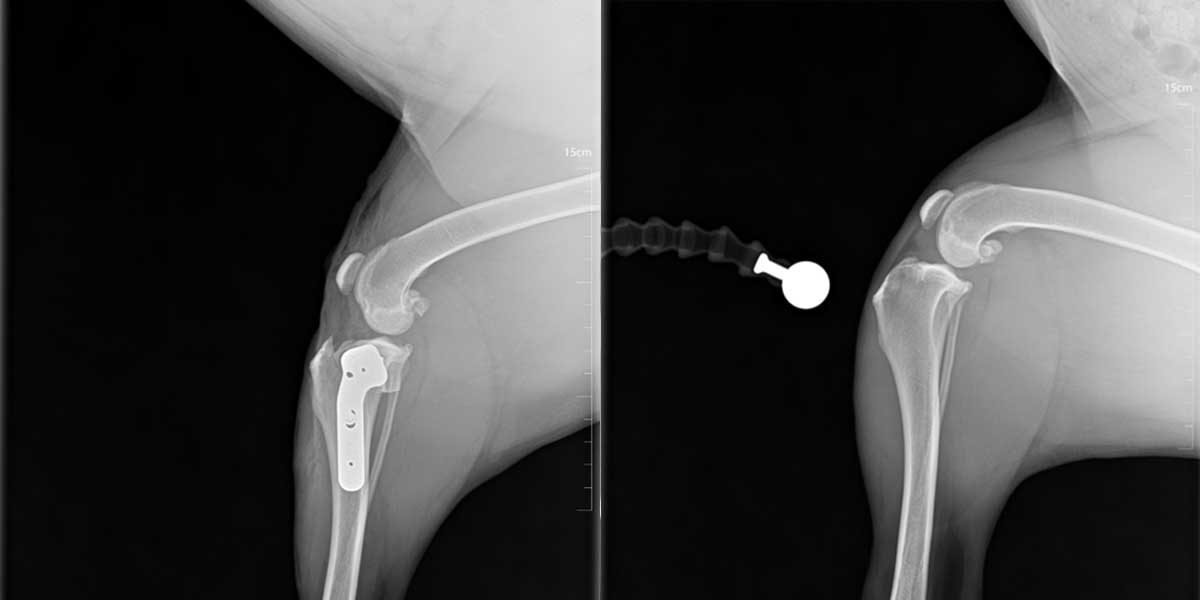

TPLO (Tibial Plateau Leveling Osteotomy) je kirurški zahvat koji se koristi za liječenje puknuća prednjeg križnog ligamenta koljena.

Tijekom TPLO operacije mijenja se kut gornje površine goljenične kosti kako bi se koljeno stabiliziralo bez potrebe za ligamentom.

Kirurg napravi kontrolirani rez na kosti, zakrene je u novi položaj i učvrsti posebnom metalnom pločicom i vijcima, time se sprječava klizanje potkoljenice pri opterećenju noge.

Većina pasa počinje opterećivati nogu unutar nekoliko dana nakon zahvata, potpuni oporavak traje otprilike 8 do 12 tjedana uz kontroliranu aktivnost i rehabilitaciju.

Prednost TPLO-a je brži i sigurniji povratak normalnom hodu, osobito kod srednjih i velikih pasa.

TPLO je danas jedna od najpouzdanijih i najčešće korištenih ortopedskih operacija u veterinarskoj medicini.

Lateralni šav je kirurška metoda koja se koristi za stabilizaciju koljena kod puknuća prednjeg križnog ligamenta.

Ovom tehnikom se umjetnim šavom zamjenjuje funkcija oštećenog ligamenta.

Šav se postavlja izvan zgloba, između bedrene (fabele) i goljenične kosti, kako bi se spriječilo kranijalno pomicanje koljena.

Koristi kod manjih pasmina pasa te kod manje aktivnih životinja, a prednost lateralnog šava je kraće trajanje operacije i manja invazivnost u odnosu na osteotomije.

Zahvat ne mijenja položaj kosti, već se oslanja na stabilnost koju pruža šav i okolna tkiva, potrebna je stroga kontrola kretanja tijekom nekoliko tjedana.